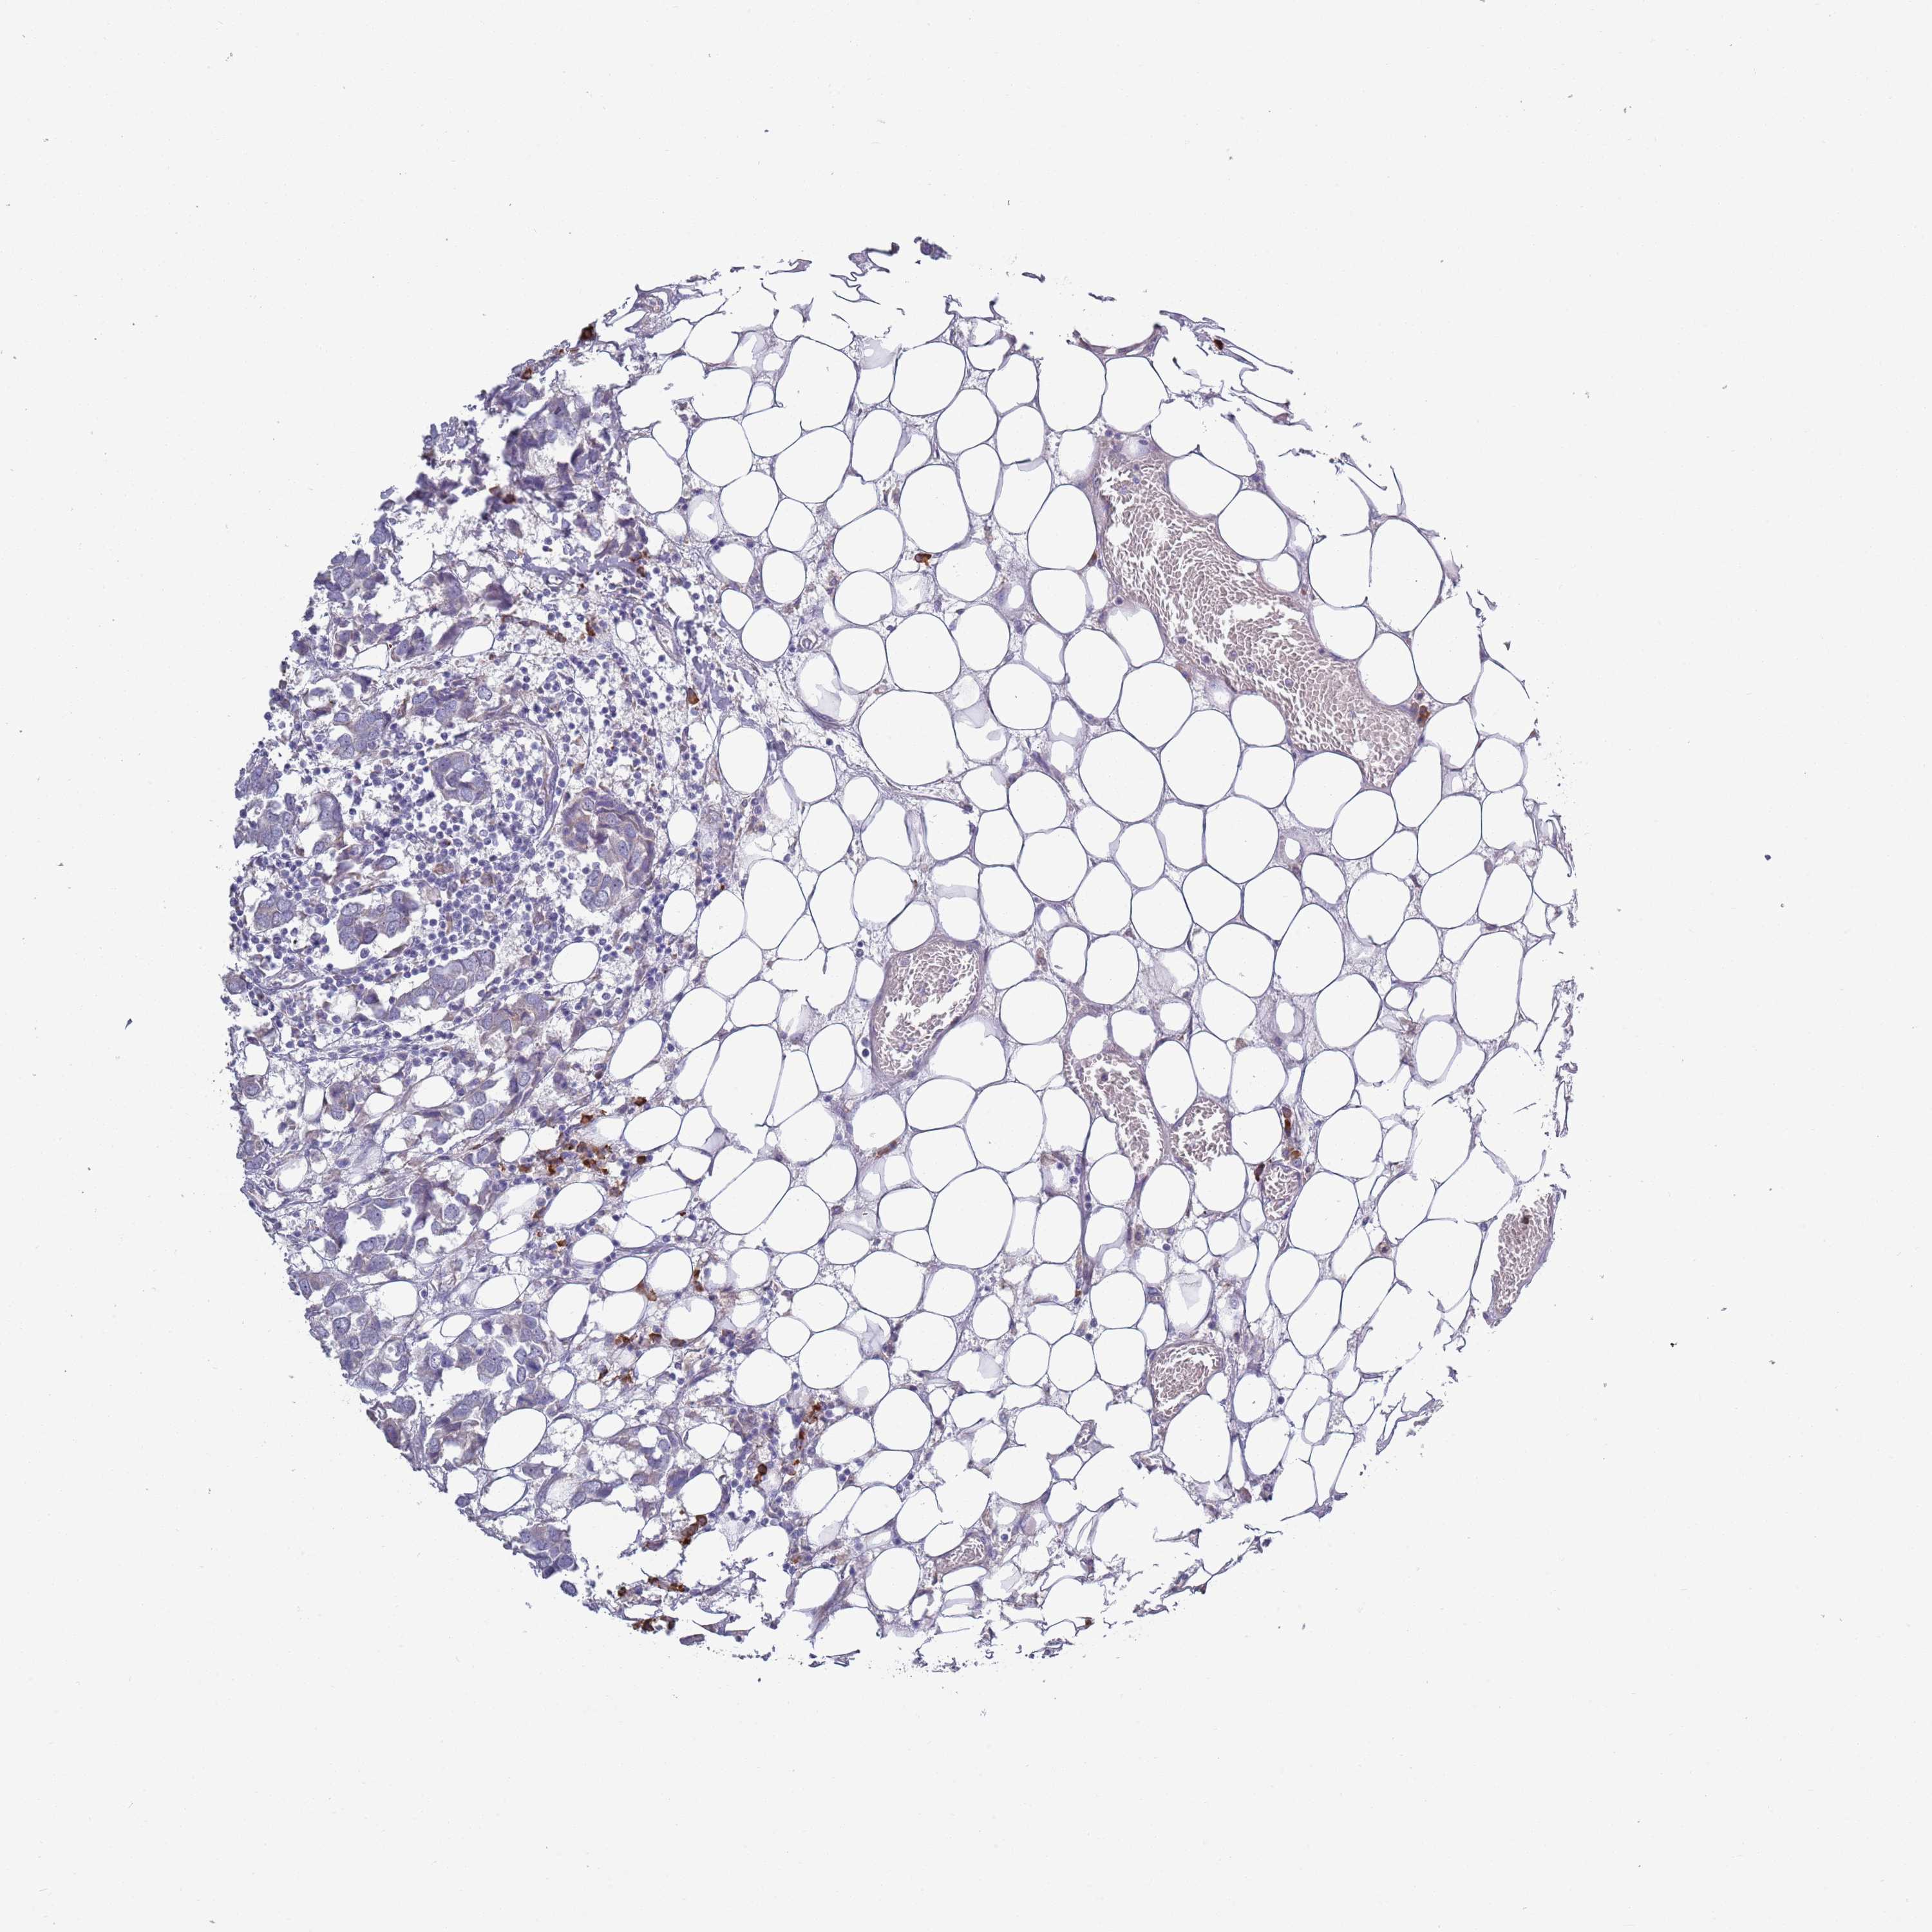

CANCER BREAST CANCER Show tissue menu

BRCA TCGA BRCA VALIDATION PROTEIN EXPRESSION